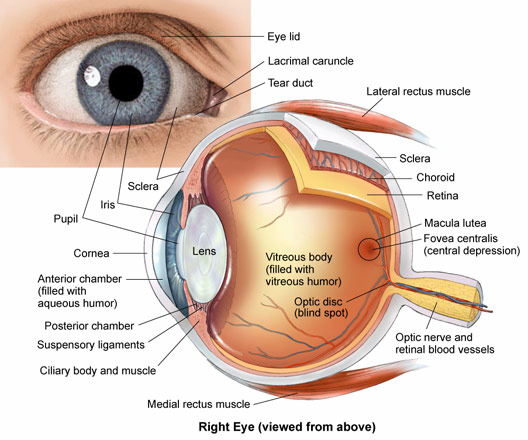

The Structure of the Eyes

The Structure of the Eyes

The eye is made up of different parts. Each part performs different roles in helping us to see. The parts of the eyes are: Iris, Cornea, Lens, Retina, Optic nerve, Pupil, Tear gland, the eye ball, Eyebrow, Eyelashes, Aqueous and Vitreous humors.

PARTS OF THE EYES FUNCTIONS

The Iris ---- This is the coloured part of the eye. It surrounds the pupils and helps it to regulate the pupils to darken or brighten.

Cornea- ----The cornea is a protective layer. It helps to keep dirt and dust away from the pupils.

Lens ----- This is the glass-like part of the eyes. It helps the eyes to see things that are so far or nearby changing their size.

Pupils- ----This is the hole in front of the eyeball through which light enters the eyes.

Optic nerve ----- This part of the eye is a sensory nerve, which links the eyeball to the brain.

Retina ----- This is a sensitive spot in the eye where images are formed.

Tear gland- ---- This gland helps to pour out tear over the front of the eye. The tears poured out, helps to wash away dusts, which enters the eyes.

Eyes lashes- ---- These are the hair at the lid. They help to protect the eye from dirt and dust.

The eye balls- ---- These are the organs of sight connected to the brain through the optic nerve.

Eye lid ----- This is the skin covering the eyeball. It can be closed to prevent foreign objects from entering the eyes.

Generally, the eye helps us to see.